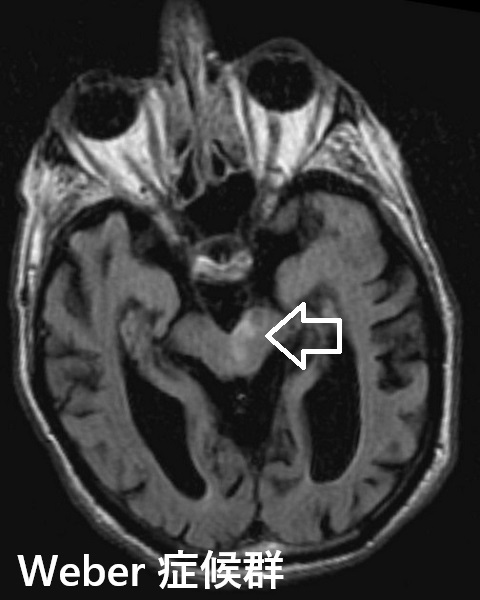

- 視床前核梗塞

- Wallenberg症候群